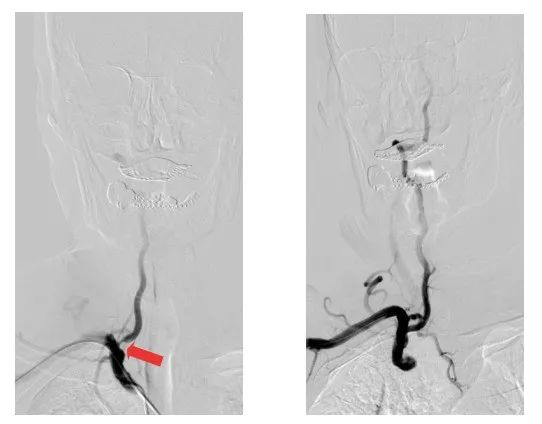

術前術后影像對比(紅色箭頭所指位置為狹窄處)

79歲的劉大爺,因反復頭昏頭暈不適來江陰市人民醫院就診。神經內科副主任醫師陸強彬為其行全腦動脈造影檢查后發現,劉大爺的右側頸內動脈閉塞,右側椎動脈開口處重度狹窄,并向右側頸內動脈代償供血。

原來,右側椎動脈重度狹窄是劉大爺長期頭昏頭暈的主要原因。醫生與患者及其家屬充分溝通后,決定施行椎動脈支架置入術。

醫療團隊僅用時40多分鐘,便通過右側橈動脈入路,成功在患者的椎動脈置入1枚支架。術后,患者的椎動脈狹窄解除,頭暈頭痛癥狀消失,即可下床活動,身體恢復良好。